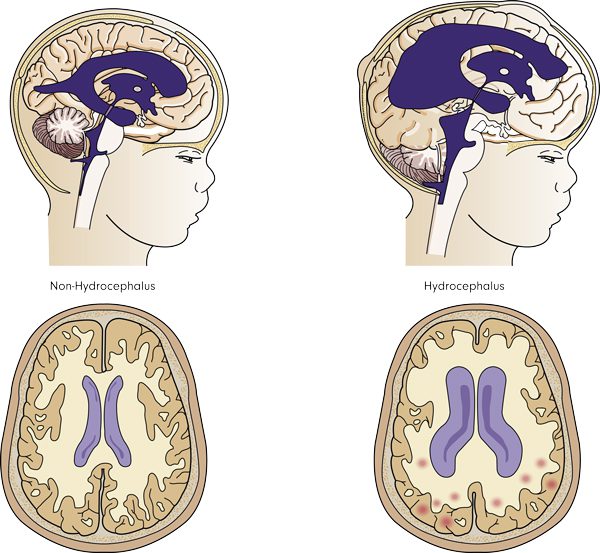

استسقاء دماغي هو اضطراب في هذا التوازن عندما يتراكم السائل في الدماغ. عادة ، يكون السبب إما انسداد التدفق أو الامتصاص غير الكافي. يتراكم السائل في الدماغ مما يرفع الضغط داخل الرأس.

يقع الدماغ في تجويف الجمجمة. إنها مساحة مغلقة ذات حجم ثابت. ومع ذلك ، فإن الدماغ لا يشغل كامل المساحة في الجمجمة. إنه محاط .(CSF) بالسائل الدماغي النخاعي

ينتج السائل الدماغي النخاعي بشكل مستمر في الدماغ عن طريق الضفيرة المشيمية. يملأ البطينات الدماغية والفضاء تحت العنكبوتية. هناك أربعة بطينات في الدماغ متصلة بالفضاء تحت العنكبوتية.

استسقاء الدماغي هو اضطراب في هذا التوازن عندما يتراكم السائل في الدماغ. عادة ، يكون السبب إما انسداد التدفق أو الامتصاص غير الكافي. يتراكم السائل في الدماغ مما يرفع الضغط داخل الرأس.

نظرًا لأن الجمجمة هي مساحة مغلقة ، حتى كمية صغيرة من السوائل الزائدة تسبب زيادة كبيرة في الضغط. يعد الضغط المرتفع في الدماغ حالة خطيرة للغاية ويجب معالجته على الفور. هناك شكل استثنائي واحد من استسقاء الرأس عندما لا يرتفع الضغط. يطلق عليه استسقاء الضغط الطبيعي (NPH) ولا يظهر إلا في المرضى المسنين.